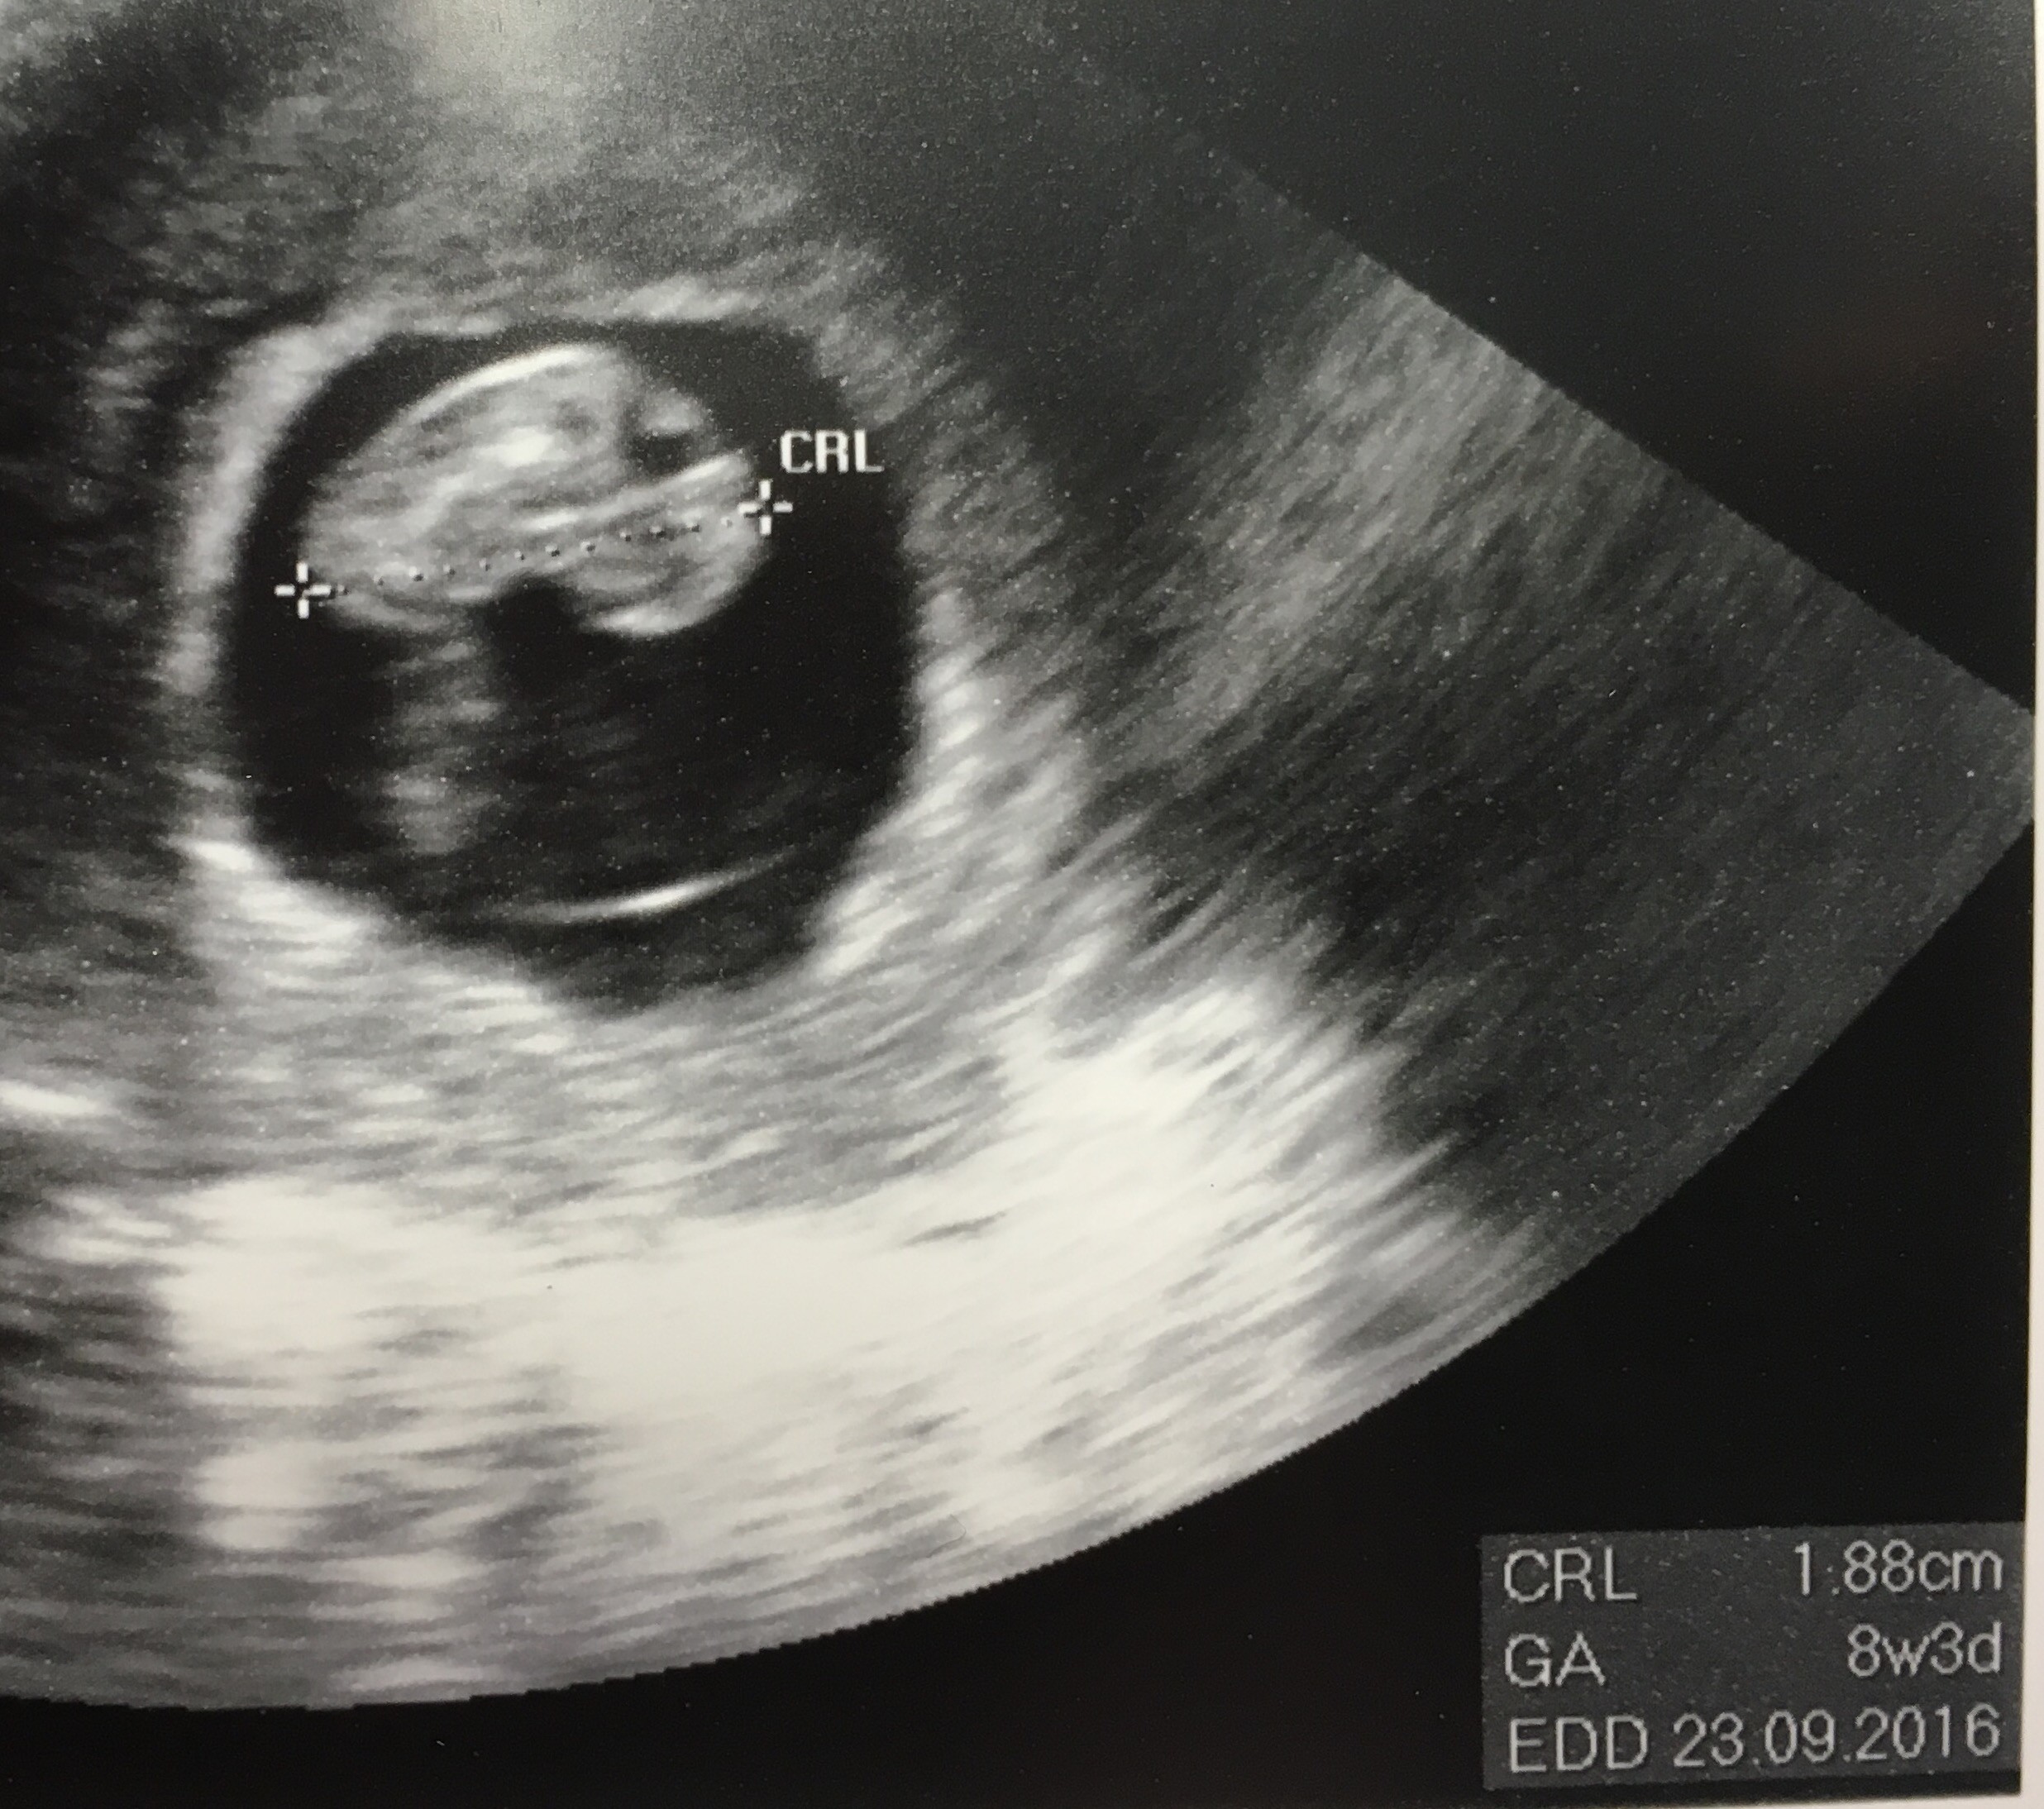

23.02 usg po hiperce